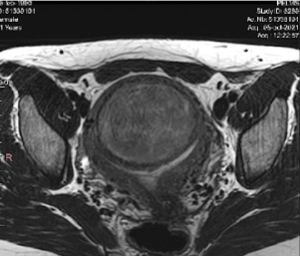

- La mida i la localització dels miomes (vegeu classificació de la FIGO)

De fet, tots els miomes de 0 al 6 són candidats a la radiofreqüència.